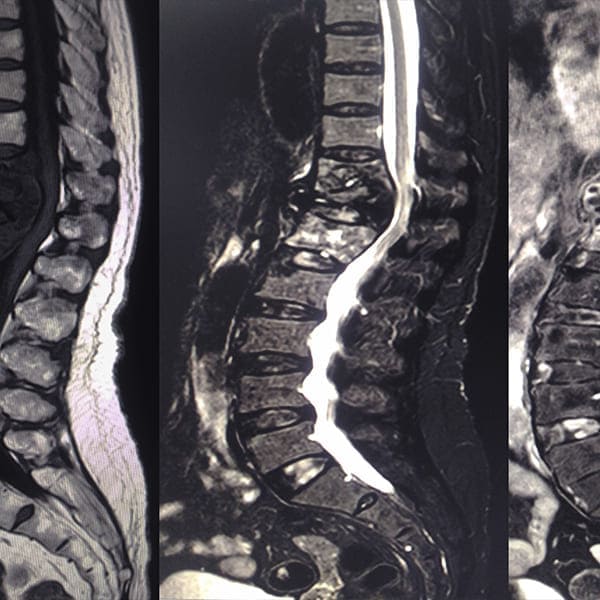

Hernia de Disco

Disectomía por Fenestración Convencional Lumbar

Procedimiento tradicional para aliviar la presión en la columna debido a una hernia discal.

Disectomía MISS o Mínimamente Invasiva Lumbar

Técnica avanzada que utiliza incisiones menores para una recuperación más rápida.

Microdisectomía Lumbar

Utiliza microscopio para tratar hernias discales con precisión y minimizar el trauma en el tejido circundante.